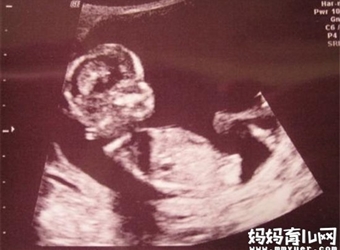

有网传,从四维彩超可以看胎儿性别。而且,四维彩超看性别的准确率很高,基本上一逮一个准,那么,事实真的如此吗?那么,四维彩超怎么看性别呢?